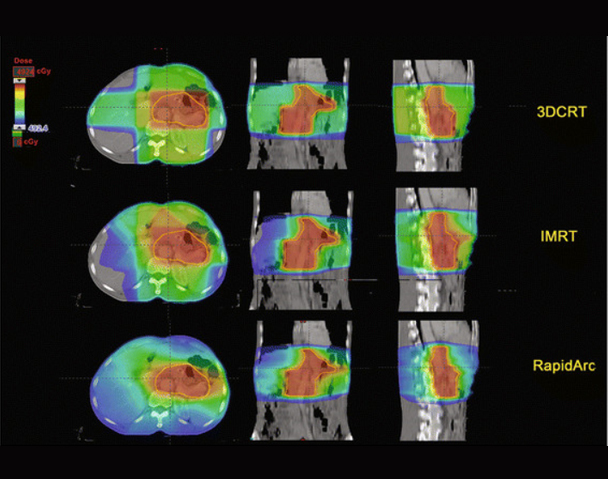

Radiation Oncologist with 7+ years of experience in Radiotherapy along with chemotherapy units. Experience in working with wide array of technologies, and expert with most advanced Linear Accelerator Radiation Modalities (Semiens, Varian Clinac ix, Elekta Versa HD, Novalis, Tomotherapy) and Eclipse version 10, Oncentra, MONACO treatment planning systems. Skilled in 3DCRT, IMRT, IGRT, RA/VMAT, SBRT & SRS.

Good experience with Cobalt and Linear Accelerator (3DCRT, IMRT, IGRT & VMAT).